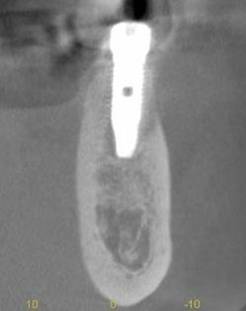

術後のCBCT

インプラントの重大な事故は下顎管から十分な距離をとれば防げます